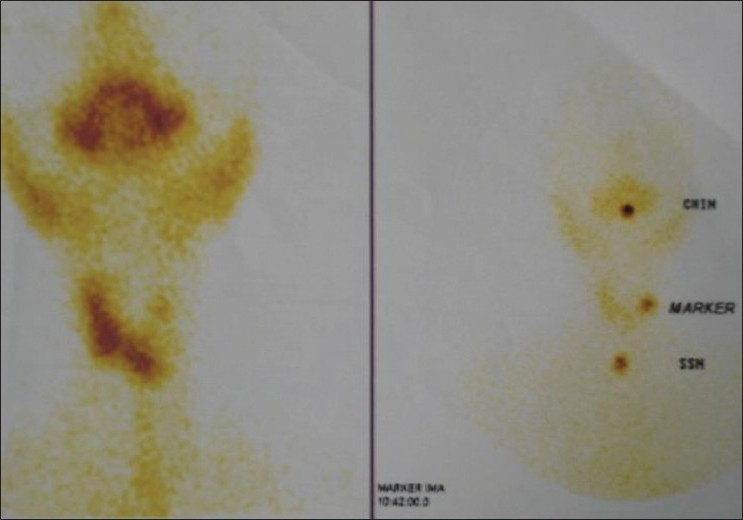

Apart from normal systemic findings and routine investigations, ultrasound of the swelling revealed a mixed solid and cystic swelling of 3 × 2 cm in the left lobe of the thyroid. Nuclear thyroid scan showed cold nodule [Figure 1]. Computerized tomography scan of neck also showed equivocal findings [Figure 2].

| Figure 1 Thyroid nuclear scan showing photopenic area in the region of the thyroid nodule on the left side of the neck

The role of RET proto oncogene mutation has been well proven in the pathogenesis of this malignancy and with multiple endocrine neoplasia syndrome (MEN).[2] When the clinical presentation is that of a thyroid nodule ,it requires careful evaluation because of about 30% incidence of malignant potential.[2] The laboratory evaluation and thyroid scinti scanning have limited usefulness for the accurate distinction between benign and malignant lesions. Thirty per cent of the cold nodules in the thyroid scan have malignant lesion. Ultrasonography provides excellent distinction between solid and cystic lesion and presence of the solid nodule should prompt the further work up to rule out malignancy. However, presence of cystic lesion is not full proof of benign condition as they can also harbor carcinoma.[7]